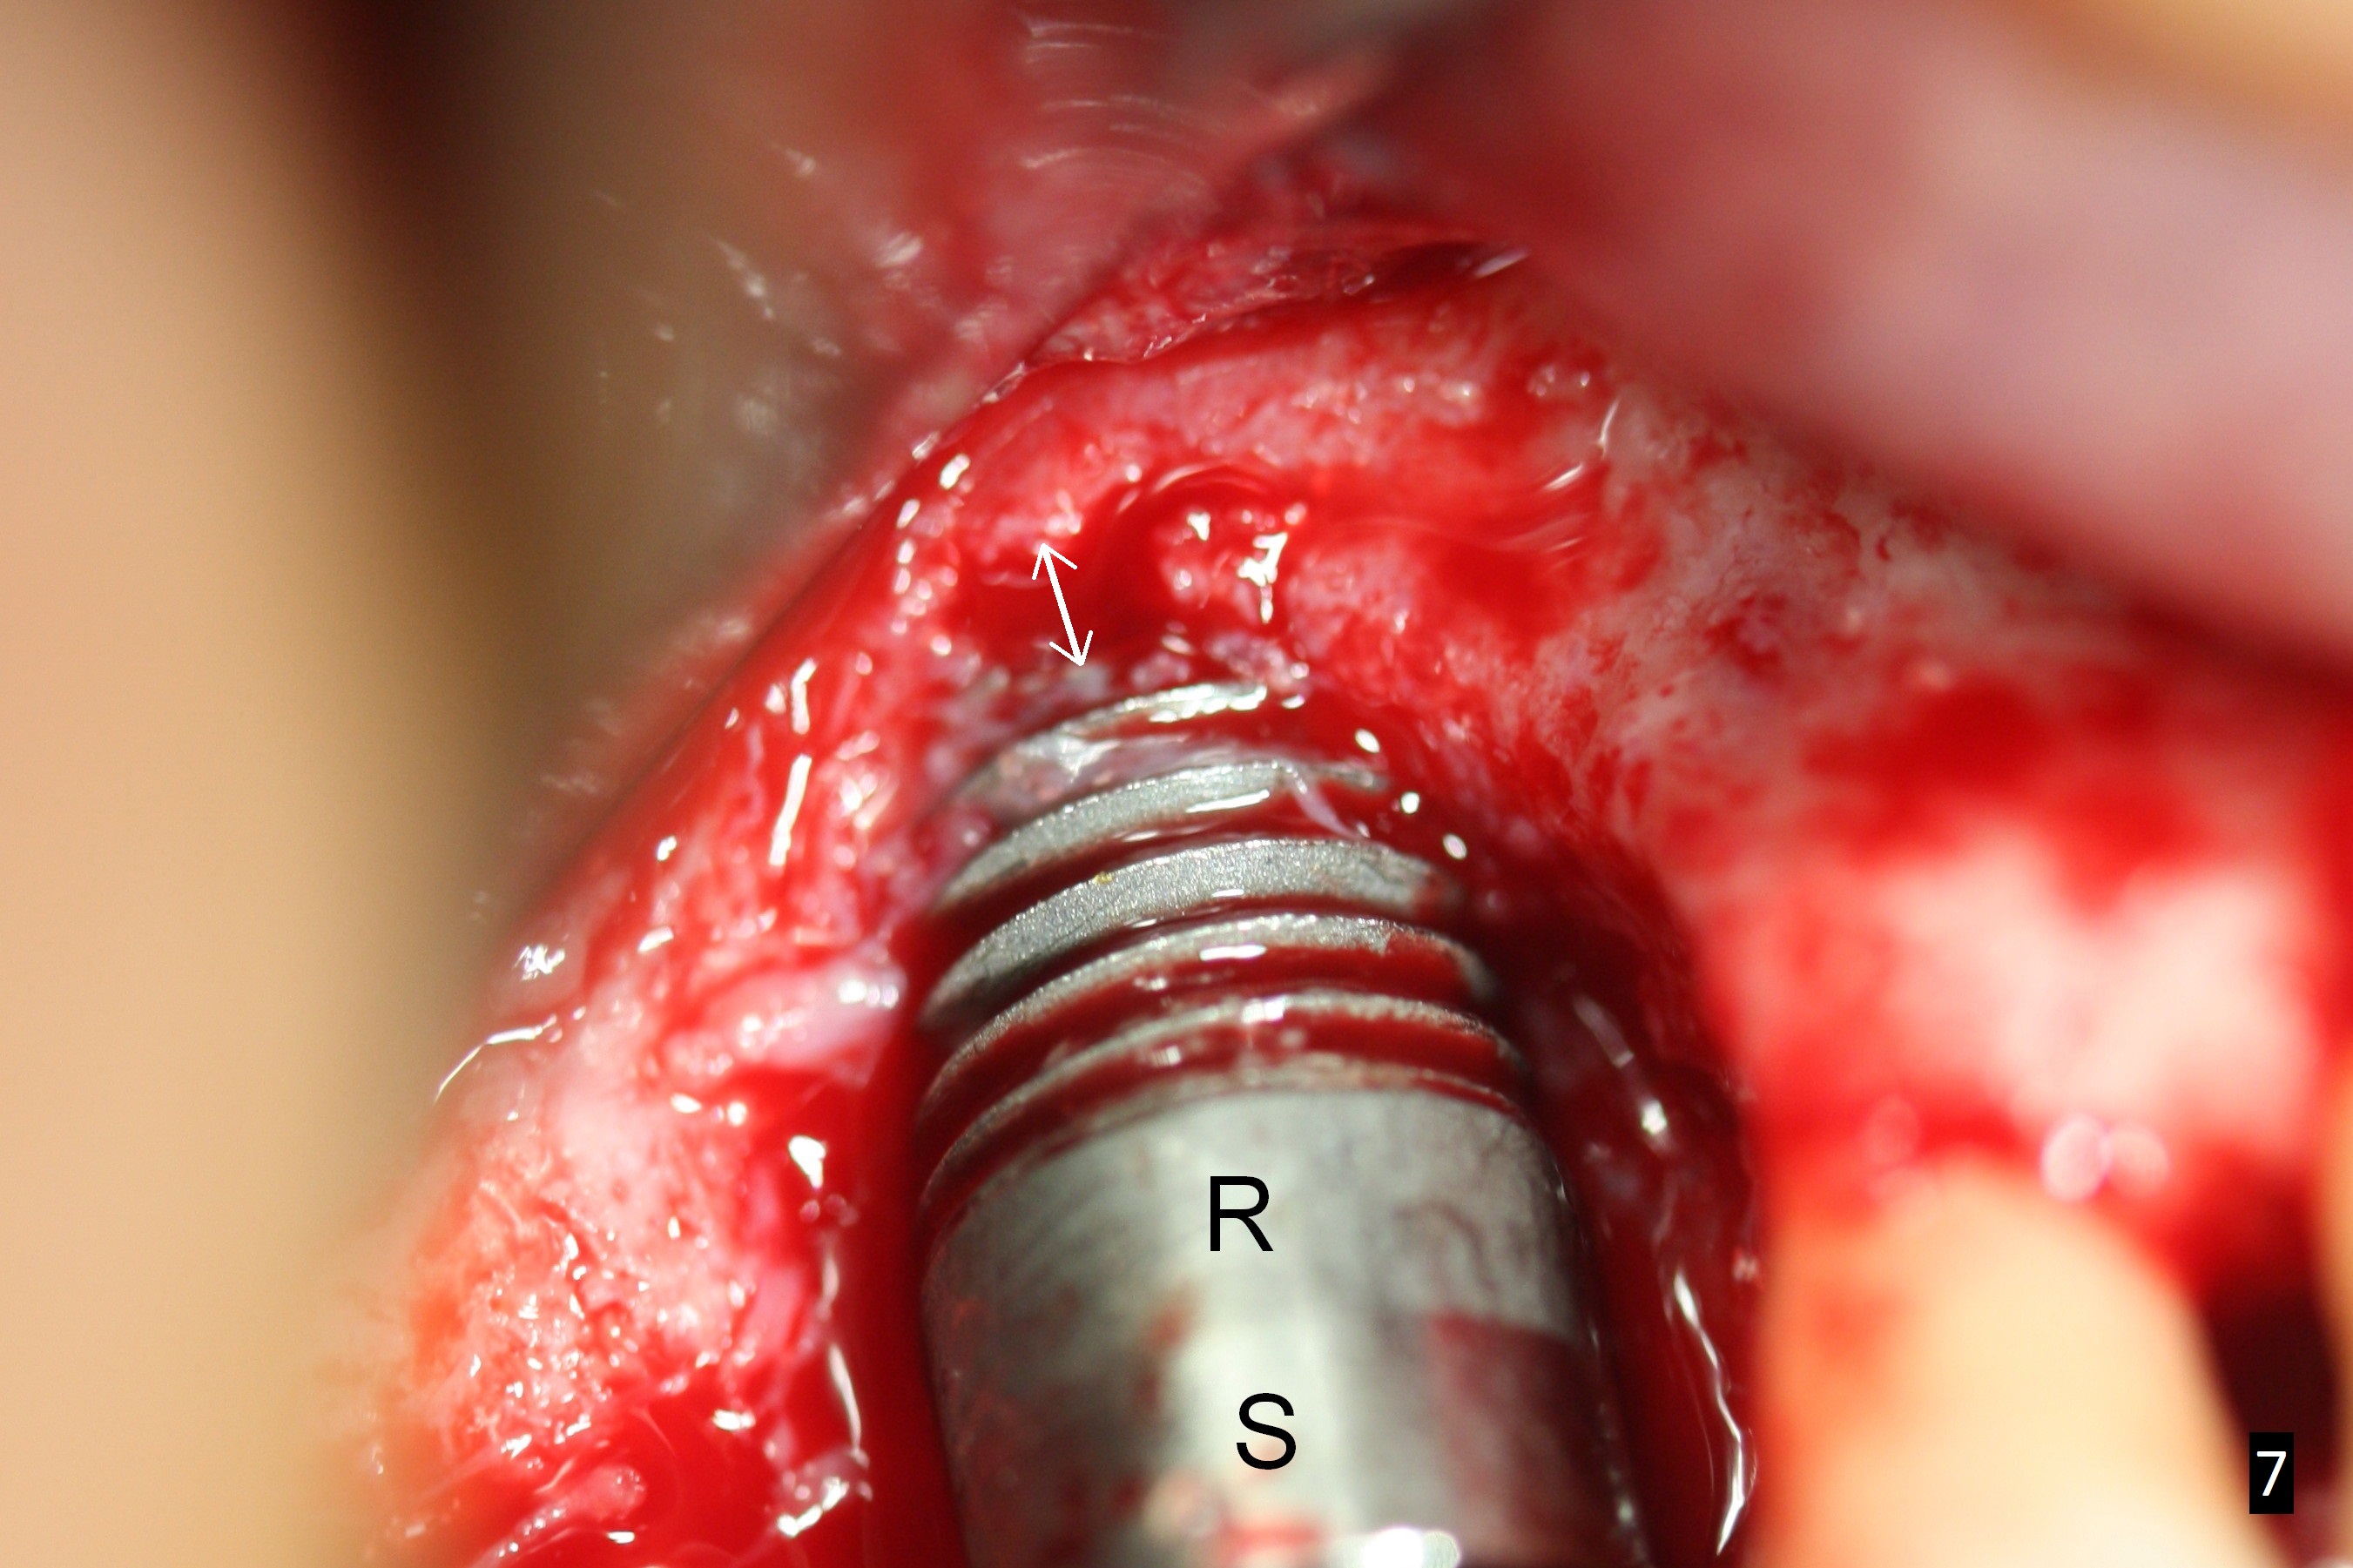

When he returns 1 month postop, the Titanium mesh is exposed asymptomatically (Fig.2). The implant threads appear not to be exposed. When to remove the mesh? A: abutment, which is removed before discharge of the patient. G: granulation tissue; *: possible the rough (R) surface of the implant (S: smooth surface).

To prevent thread exposure complication, the implant should have at least 1-2 mm buccal clearance (gap (Fig.7 double arrows)). Place a relatively smaller implant (~6 mm) as palatal as possible. Pack bone graft in the remaining gap solidly (covering implant threads buccally and interproximally, Fig.8 (green circles)).